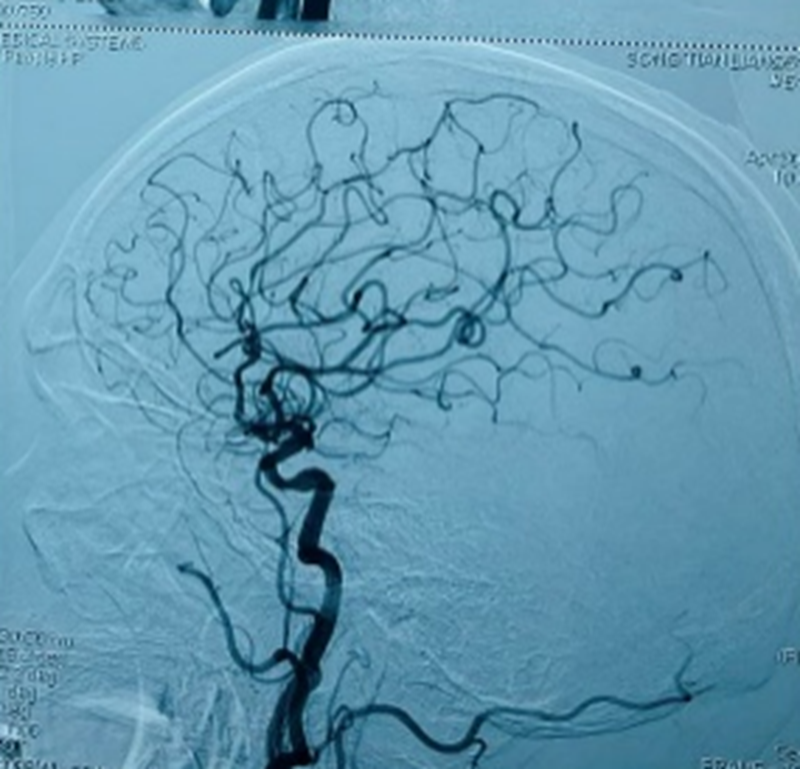

手术由神经内科(介入)副主任司君增副主任医师主刀,整个过程耗时40分钟,通过局麻下股动脉穿刺将支架精准植入狭窄部位,成功修复了狭窄的颈动脉,恢复了正常的血流通畅。术后即刻造影显示,患者右侧颈动脉血流完全恢复正常,术后密切监测血压及有无不适,在神经内一科全体医护人员的共同管理下,患者术后恢复良好,无相关并发症的发生,观察3天后康复出院,患者家属表达了感谢。